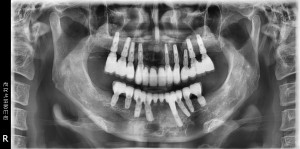

최종 보철물까지 올리고 난 후 구강 내 사진입니다.

평상시의 교합 뿐만아니라 좌우로 아래턱을 크게 움직였을 때도 불편함이 없습니다.

이후 환자분은 정기적으로 체크를 받고 계시고

이전에 좋지 않았던 구강위생도 계속적인 구강위생교육으로 많이 개선되었습니다.